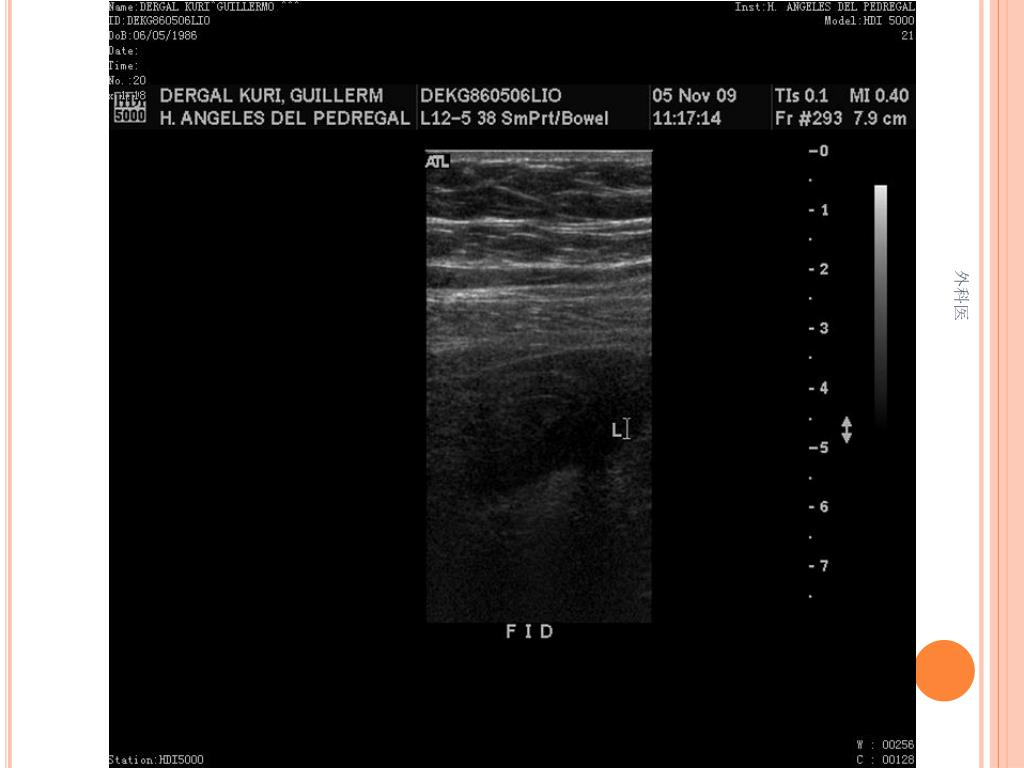

21. 外科医

44. Tips • Leucocitos Mas de 20000/ml • Mas de 20% de la apéndices no se llenan con el bario por enema. • USG sensibilidad del 85% y Especificidad de mas 90% para Apendicitis Aguda. • TAC de Abdomen cortes de 5mm, sensibilidad y especificidad del 90% para dolor abdominal. • Analisis de 75000, taza de apendice negativa de 6% Hombres y 13% Mujeres 外科医